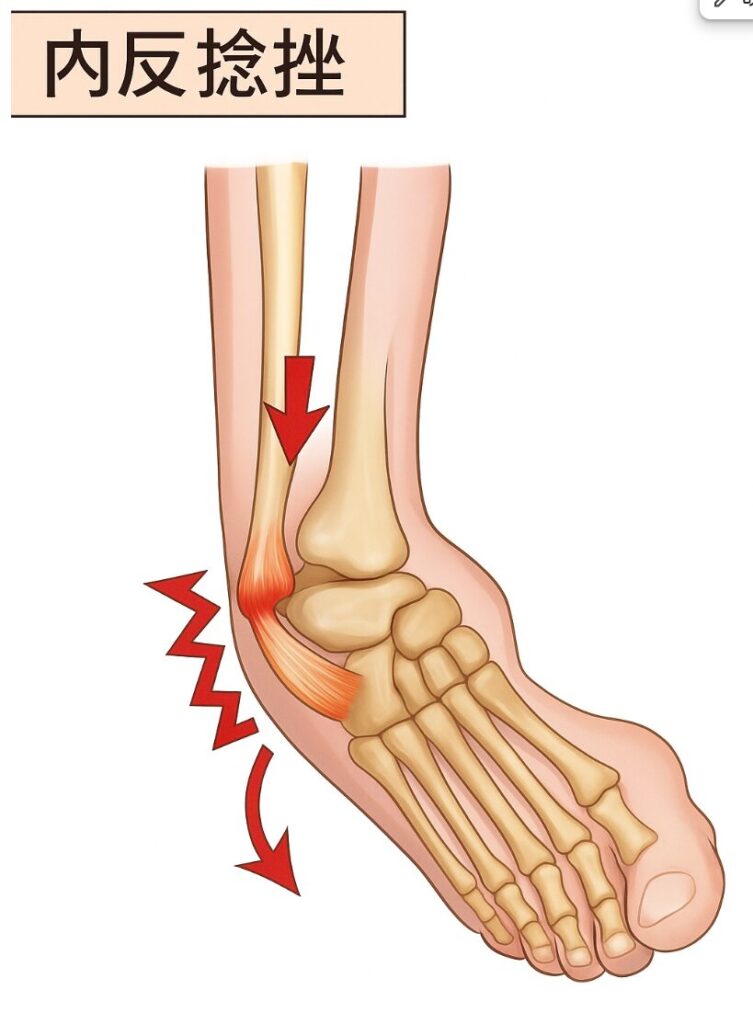

①捻挫とその原因

まず「捻挫(ねんざ)」とは、

関節をひねって、靭帯(じんたい)という関節を支えるスジを痛めるケガのことです。

特に多いのが「足首の捻挫」です。

階段を下りているときにグキッとひねったり、

段差でバランスを崩したりして起こります。

少し専門的に言うと、

「関節に強い力が加わって、骨は折れていないけれど、靭帯や関節のまわりの組織が傷ついた状態」

そのことを“捻挫”と呼びます。

つまり、骨折ではないけど、関節を守るスジが伸びたり切れたりしている状態です。

特に下の画像のように

内側に入れた時に片方だけ明らかに入る

もしくは止まらない

というのはかなり問題ですね。